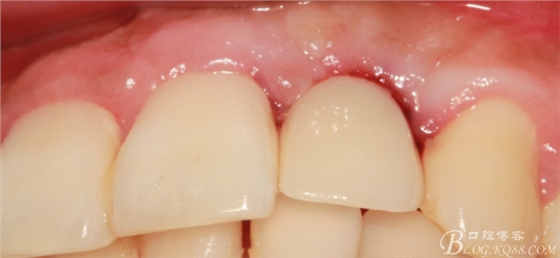

兩個(gè)月后戴入永久修復(fù)體。

戴入永久修復(fù)體當(dāng)天口內(nèi)照,雖有小瑕疵,但患者很滿意。